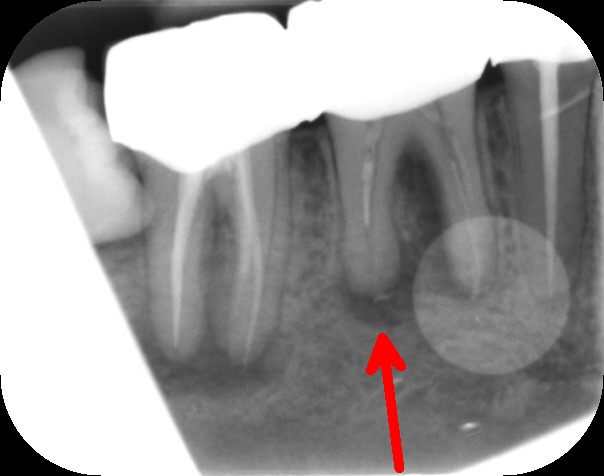

The main goal of endodontic therapy is to remove necrotic pulp tissues, to eliminate or significantly reduce microorganisms and their toxic products from the canals and also to prevent inflammatory lesion in the periapical area. Endodontic therapy protects the tooth from further invasion from microorganisms. If the tooth is left without treating, the infection may spread and cause pain and swelling.

Files of different sizes are used to eliminate bacteria and infection and to shape the canals. The canals are disinfected thoroughly with irrigants and later the canals will be sealed in 3 dimensions with a special medicament called gutta-percha to prevent reinfection of the tooth and the access cavity will be sealed with a temporary filling.

After a few weeks, the tooth will be checked and when all the infection has cleared, a crown will be usually required to protect the restore the tooth to function.

Studies have shown thorough cleaning with instruments, disinfection and sealing the canals contribute to the successful healing of the infection and this success is reported as 95%.